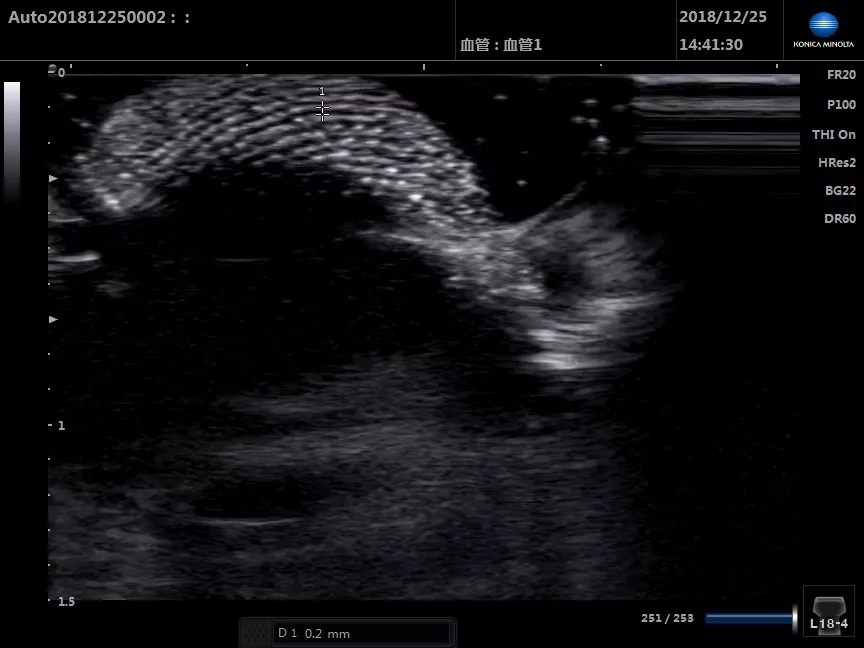

超聲下的姆長屈肌腱(短軸)

■ 患者,中年女性,左圖為患側,右圖為健側,患側肌腱明顯增粗